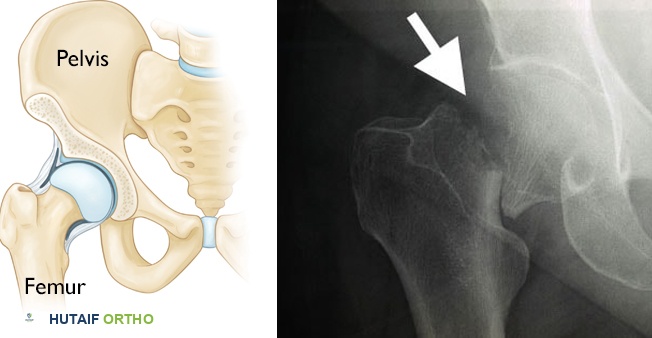

فحوصات التصوير:

- الأشعة السينية (X-rays): يمكن أن تكشف عن تشوهات هيكلية أو علامات الكساح، ولكنها ليست دقيقة في قياس كثافة العظام.

- قياس كثافة العظام (DXA Scan أو DEXA Scan): يُعدّ هذا الفحص هو المعيار الذهبي لقياس كثافة المعادن في العظام. ومع ذلك، لا يُجرى بشكل روتيني للأطفال إلا في حالات خاصة جدًا، مثل: